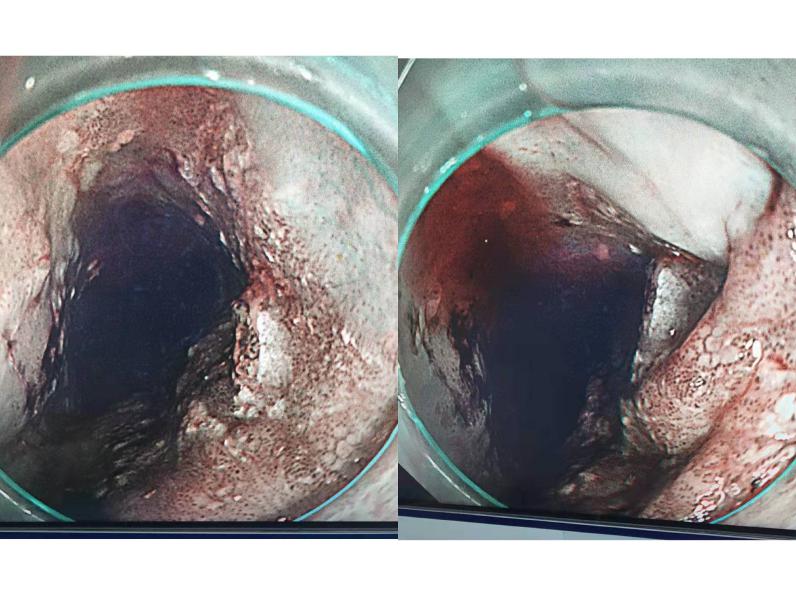

术前胃镜下食管病变部位

剥离的食管病变组织

三月中旬,龙山县62岁的彭阿姨带着满心的感激来到天心阁院区消化内科门诊复诊,彭阿姨2020年底发现食管鳞癌,本以为要经历开胸开腹的大手术,在消化二科经刘鹏主任会诊后,接受了ESD(内镜粘膜下剥离术),手术获得成功,免除了开刀之苦。

刘鹏主任介绍,彭阿姨患的是食管上段早期癌症,ESD术实施全周剥离,十分成功,食管早癌全周型的患者,术后极易出现食管狭窄,需要再次手术扩张食管,而彭阿姨术后四个月复查的胃镜显示,食管恢复正常,未出现狭窄。